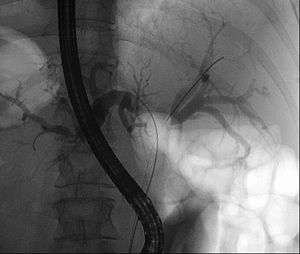

Klatskin tumor during ERCP. In the left and right biliary system wires were placed. Both parts were injected through a tube with contrast. The lack of contrast in the area of the confluence is clearly visible.